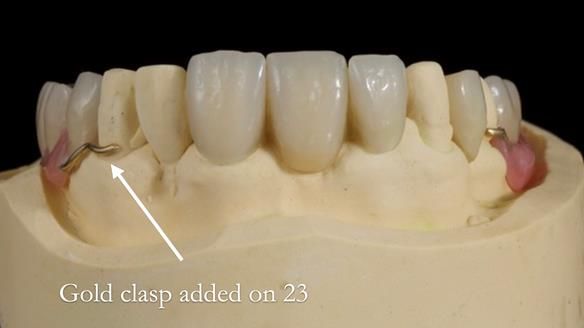

This edition features the case of Edgar, who sought help for a poorly fitting, acrylic-based partial denture that rocked, affected his speech, and caused discomfort. After considering various treatment options, including dental implants, Edgar opted for a metal-based removable partial denture, designed by myself with input from my technician, Rowan Garstang.

Despite significant improvements in comfort and aesthetics, Edgar expressed dissatisfaction with the denture's slight movement during certain jaw movements. This case underscores the importance of setting clear expectations, communicating limitations early, and ensuring both the patient and I are aligned on what can realistically be achieved. I must also be careful not to exaggerate the benefits of the treatment, to avoid creating false expectations.

Treatment Process: I provided the clinical work while Rowan Garstang delivered the technical aspects. The treatment required fifteen visits to fit and review Edgar.